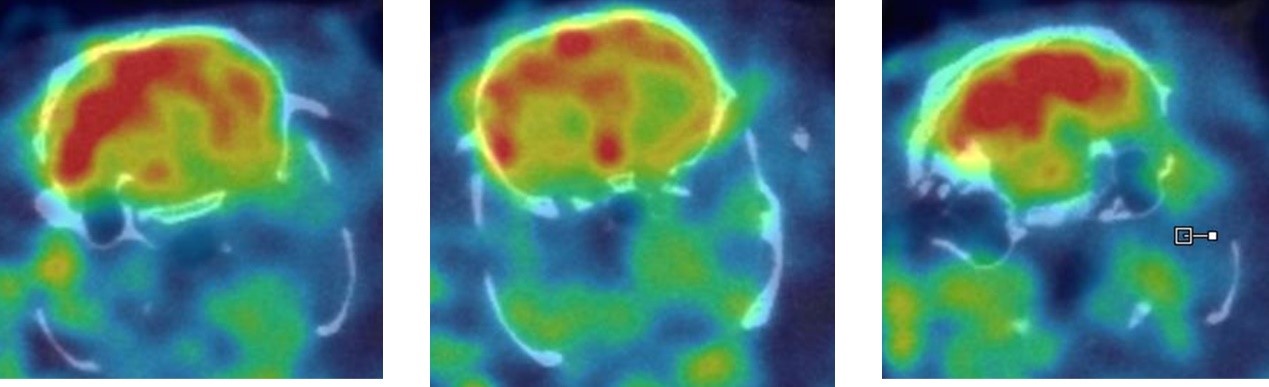

1、神經(jīng)系統(tǒng)SPECT成像

大鼠腦部SPECT成像:99mTc-HMPAO:腦血流灌注顯像劑,用于腦血管疾病,腦外傷,癲癇,癡呆癥,腦死亡的診斷;用于精神疾病的腦功能及正常腦生理功能活動的研究。進入腦組織的99mTc-HMPAO構(gòu)型改變而轉(zhuǎn)變成水溶性化合物,無法再次通過血腦屏障而滯留在細胞內(nèi),因此能在腦內(nèi)長時間滯留。120 MBq,30 min uptake,30 min SPECT。

神經(jīng)系統(tǒng)成像.jpg